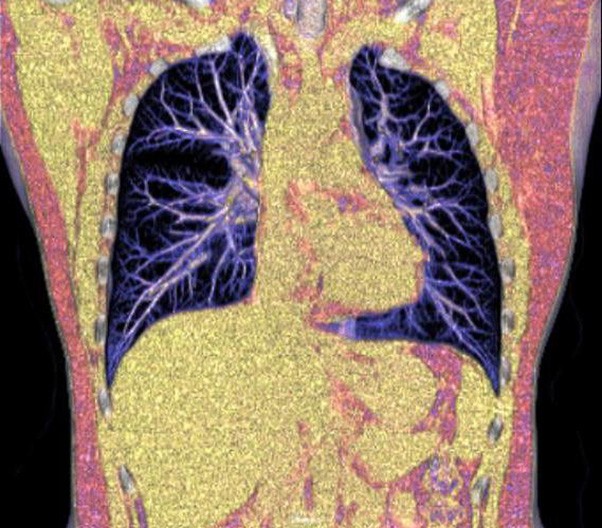

The 1024-pixel image matrix brings superior image clarity (0.6 mm slice thickness) and stimulates the early detection of small lesions, thus improving diagnostic reliance.

ScintCare CT 16 incorporates an entirely digital integrated ScintiStar detector, which was solely developed by MinFound, from material to the whole structure design, based on the technical know-how of our skilled scientific team. The system produces high-resolution images with a low radiation dose and an excellent signal-to-noise ratio.

NDI NanoDose Iteration Algorithm (NDI) is an innovative iterative technique for image reconstruction that takes full advantage of deep learning in anatomical structure in image space as well as model-driven iteration involving tube and detector in projection space, with the aim to generate sharp and high-resolution images at the lowest possible dose.